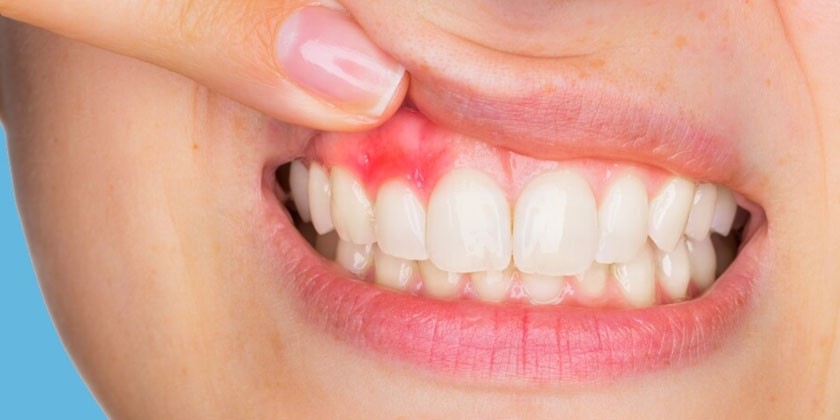

Симптомы гингивита

Заболеванию характерен зуд десен во время приема пищи – непреодолимое желание почесать слизистую около зубов. На фоне зуда возникает болезненность десен, которая приводит к затруднению приема пищи. Боль усиливается во время чистки зубов, иногда влияет на речь, может повышаться температура до 39 градусов. Другие характерные признаки гингивита:

- гиперемия и отек десны в области нескольких или всех зубов;

- кровоточивость десен;

- отечность и покраснение слизистой;

- кровоточивость десен при чистке зубов;